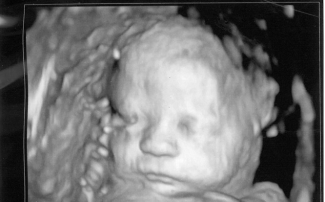

"Každá ľudská bytosť ma právo na život od okamihu počatia," uviedol kongresman Mario Pérez, ktorý toto opatrenie predstavil.